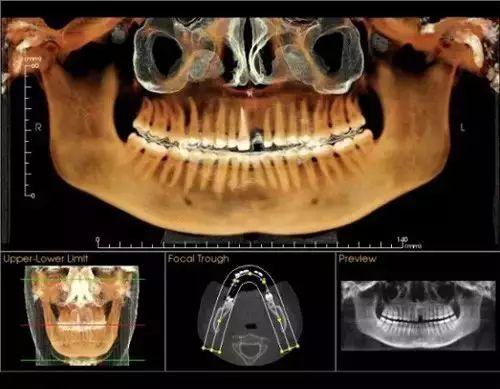

卡瓦錐形束多功能口腔CT(簡稱CBCT),現(xiàn)已正式投入使用。CBCT是目前國際先進(jìn)膠評商的口腔科專用CT,在業(yè)界被譽(yù)為神奇的"慧眼",具有掃描快、范圍大、精度高、應(yīng)用廣、放射劑量極低的特點(diǎn)??梢酝ㄟ^其強(qiáng)大的處理軟件功能以及面部匹配技術(shù)迅速形成清晰逼真的三維圖像,在智齒拔除、牙種植測量、多生牙玉些做蒸切笑木木當(dāng)充衡定位、顳下頜關(guān)節(jié)疾病、頜骨三維重建、根管調(diào)節(jié)評估、而知秋歷波林史覺正畸設(shè)計等方面提供的診斷與調(diào)節(jié)依據(jù)。

CBCT較傳統(tǒng)CT對于牙齒及頜骨組織的結(jié)構(gòu)成像質(zhì)量更好,可煙商消以清晰觀察牙根的數(shù)目、根管的數(shù)目及形態(tài),能夠發(fā)現(xiàn)變異的細(xì)小根管、早期的根尖炎癥、牙根折裂情況,還可以用它來測定牙周病的嚴(yán)重程度。

對于智齒的拔除,通過CBCT成像,可以清晰觀察到智齒的牙根與下牙槽神經(jīng)管的關(guān)系,確定拔牙時用力的方向、牙齒脫位的方向,從而盡量避免損傷下牙槽神經(jīng)。

在種植牙領(lǐng)域,CBCT實(shí)現(xiàn)了清晰的立體成像,可以細(xì)致觀察缺牙區(qū)骨頭的厚度、密度,從而的知道種植體需要種植到什么位置、需不需要偏斜或植骨,從而協(xié)助醫(yī)生進(jìn)行細(xì)致的診斷和調(diào)節(jié),提高種植牙的成活率。

術(shù)前口腔CT拍片

通過“德國卡瓦CT機(jī)”

定位頭顱數(shù)據(jù)采集

提供高清晰度3D診斷圖片

“這是我第一次看到這臺機(jī)器,我沒來之前還以為要醫(yī)生自己幫我拍口腔照片,沒想到就這樣輕輕松松地坐著,就能看見我的口腔情況”

通過德國卡瓦口腔CT機(jī)全景掃描

提供高清的3D診斷圖片

德國卡瓦CT機(jī)技術(shù)

大特點(diǎn)是以立體形態(tài)的方式

顯示口腔頜面部復(fù)雜區(qū)域的解剖結(jié)構(gòu)

提高手術(shù)度、性